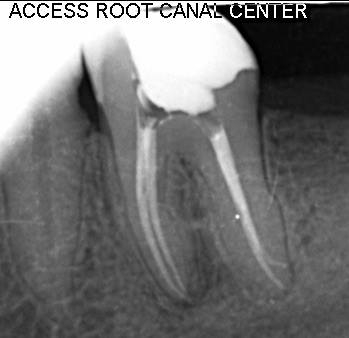

Rotary Endo with Post - Core & Rubberdamalogy - Dec 2018

Got a very clear idea of RCT procedure ; Excellent overall experience. LIVE RCT on patient was very clear with clear demo